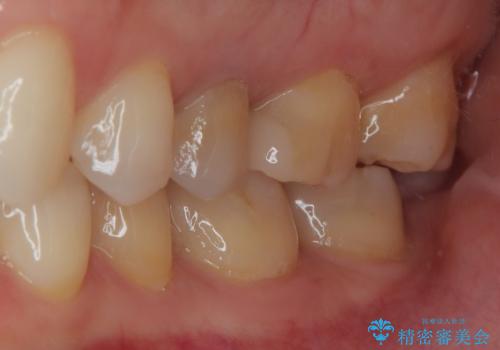

拡大鏡視野下で、金属の詰め物(メタルインレー)、保険のプラスチック、虫歯の除去を行い、セラミックインレーに適した形に整えました。

歯と歯茎の間に圧排糸と言われる糸を入れてシリコーン印象材にて精密な型どりをしました。

セラミックインレーの装着時には、唾液の侵入を防ぐために、ラバーダム防湿を行いました。